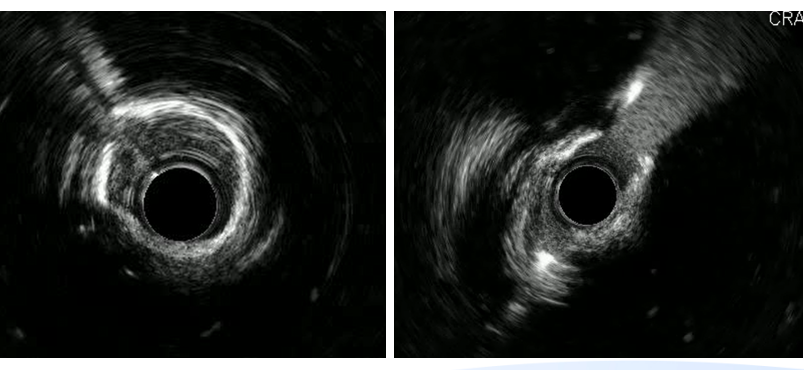

左主干-回旋支行IVUS检查;

回旋支近中段可见弥漫性狭窄伴有360°环形钙化;

回旋支开口面积2.1平方毫米;

左主干-前降支IVUS导管不能通过。

切割球囊切割后行IVUS检查提示钙化环有所断裂,回旋支开口狭窄仍严重,遂决定使用2.5mm NC球囊高压扩张。

回旋支支架植入后因支架及钙化原因,IVUS导管无法推送至中段以后,遂仅对回旋支开口支架IVUS检查。

回旋支开口支架后扩后行IVUS检查:支架贴壁膨胀良好。